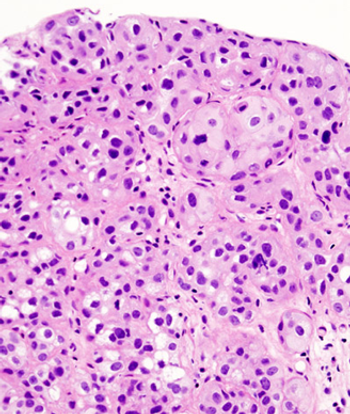

Phase II study results found that half of patients with relapsed or refractory urothelial carcinoma responded to treatment with pazopanib and paclitaxel.